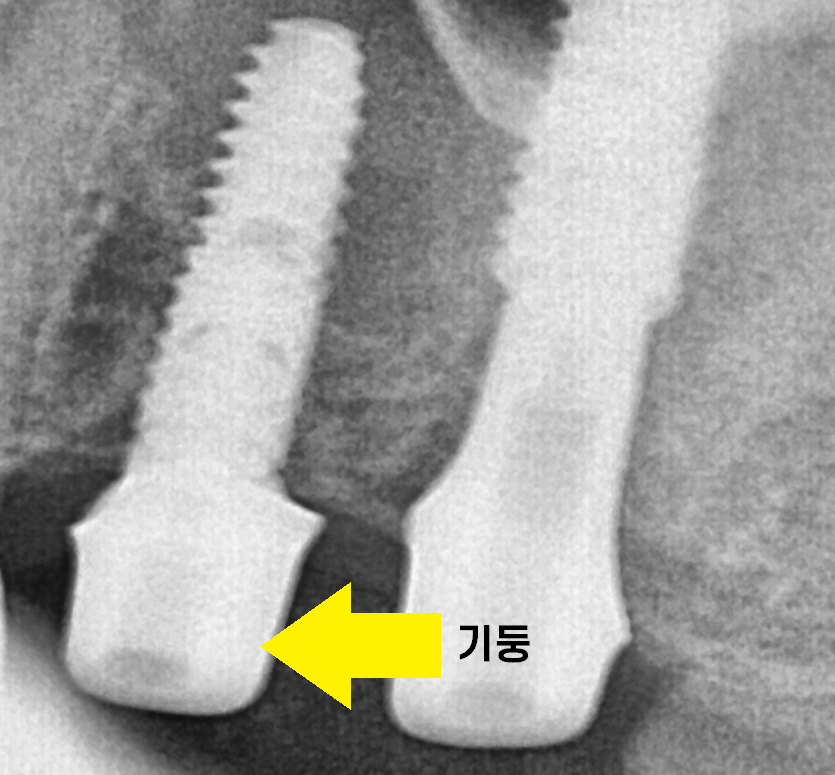

뼈 안에 임플란트는 심어져 있고

임플란트 위에 "커버스크류" 라는 재료를 끼워둡니다.

이 커버스크류라는 재료를

잇몸 밖으로 꺼내는 것이 2차 수술인데

꺼내고 나면 이런 모습이에요!

작은 기둥을 연결하는 것이 임플란트 2차 수술 과정입니다.

기둥을 연결해준 뒤 임플란트 머리 뽄을 뜹니다.